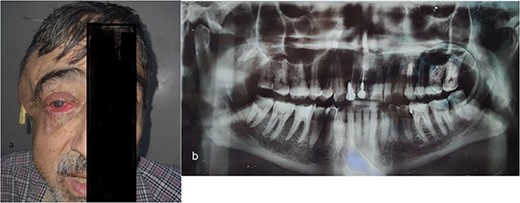

(a) The right masticatory, buccal and temporal regions are markedly swollen, and a drain has been inserted into the abscess cavity in temporal region. There is obvious pus oozing from the right eye, and the right eyelid and cornea both exhibit redness and edema. (b) Panoramic radiograph revealed periapical abscess, lateral large deep caries with pulp involvement in the third right mandibular molar tooth.

At admission, 1 month and 1 week after initial symptom onset, the patient’s overall health was poor, with arterial hypotension, fatigue and fever. During the ophthalmic exam, the right eye showed exophthalmos, a purulent discharge from the lateral canthus, a visual acuity of 0/10 with only light perception, an upper corneal density with lateral thinning and herniation of the iris, with the contents of the uvea protruding through a corneal ulcer and upper eyelid ptosis (Fig. 1a).